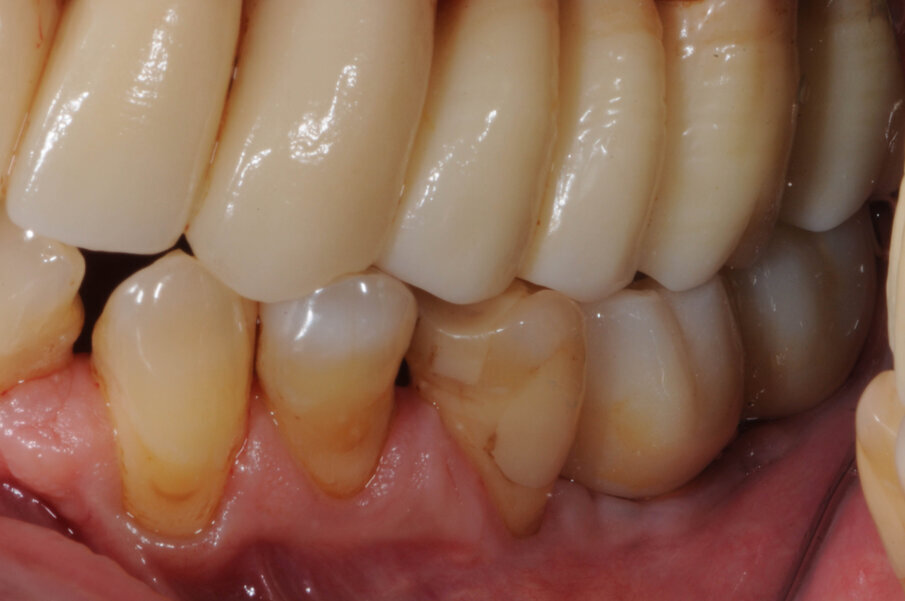

La paziente donna di 72 anni in buono stato di salute generale si presentò alla nostra attenzione per la mancanza dei denti nei settori inferiori posteriori (Fig. 1). Dalla radiografia OPT si notava che nel settore 4 era presente una zona di radiotrasparenza causata dalla recente perdita di due impianti dentali a causa di periimplantite. Si decise pertanto di iniziare a ripristinare il settore 3 (Fig. 2).

Dopo tre settimane i tessuti attorno agli impianti apparivano sani e privi di infiammazione. Era presente anche una banda di tessuto cheratinizzato. Fu presa un’impronta con tecnica del cucchiaio aperto e due settimane dopo furono consegnate due corone in zirconio avvitate. Il controllo radiografico evidenziava una buona stabilità dell’osso crestale (Figg. 10-13).